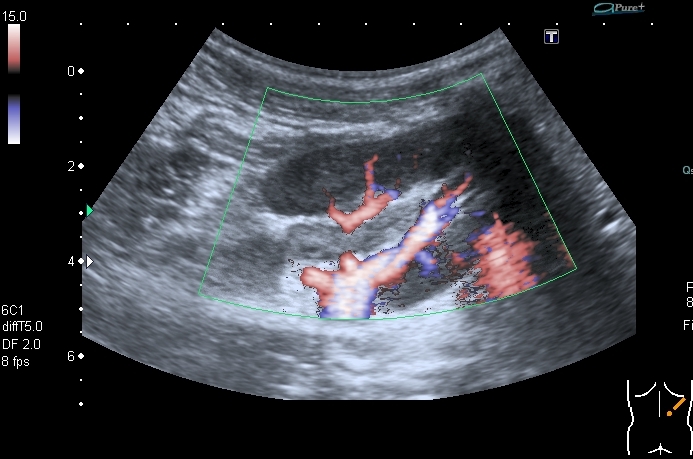

Поэтому правильнее отталкиваться от того что мы видим. А видим мы классические признаки, которые встречаем чаще всего при воспалении ЧЛС - признаки пиелита - признаки отека стенок ЧЛС на фоне воспаления. Здесь аналогичная картина, но, вероятнее всего, вызванная травмой - надрыв - разрыв -нарушение целостности стенки ЧЛС - отек - асептическое воспаление.

По-другому я объяснить изменения пока не могу.

По сему согласен с заключением Др Алекс.

Какова вероятность повреждения стенки ЧЛС без повреждения паренхимы и формирования урогематомы при непямой травме?

Повреждение паренхимы в данной ситуации присутствует (контузия как минимум), но может быть и разрыв, направленый не наружу, а в сторону ЧЛС.